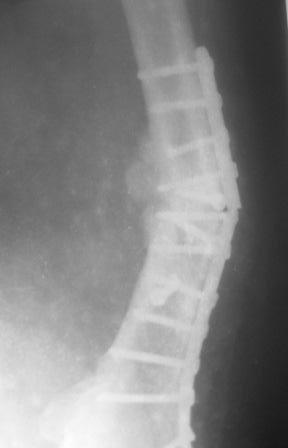

Обратился больной 54г. Травму получил в ноябре 2007г. Оперирован в

Алмате (Казахстан). Через 2 мес. гипс снят, потом еще гипс на 2

месяц, с тех пор ходит двумя костылями, последние время беспокоит

усиливающаяся боль и деформация.

Локально: укорочение ноги на 3,5см, умеренная отечность и вальгусная

деформация, умеренная болезненность, патологической подвижности почти

не определяется, но имеется наружная ротация конечности на 15гр.

Наш план БИОС, но так как при удалении пластини зона ложного сустава

открывается, для уверенности производить костную пластику (аутографт

или хотя-бы по Хахутову) ??, еще как устранить ротацию?